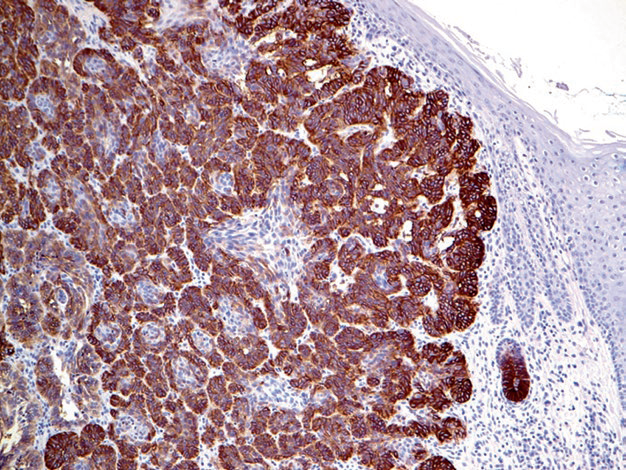

Figure 1. Basal cell carcinoma, strongly positive for Ep-CAM. Note that epidermal cells in the image do not express this marker.